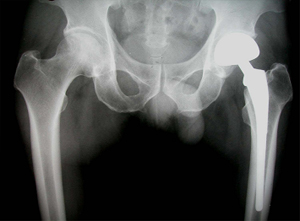

10일전 본 대학병원 OS에서 Lt. total hip replacement(THR) revision OP를 시행한 환자의 보행을 위해 물리치료 의뢰를 받았습니다. 당시이 환자의 담당 물리치료사입니다..

상기 환자는 46년 전부터 고관절 통증이 있었으며, 12년전 Lt. total hip replacement(THR)을 받은 분으로 2년 전부터 통증으로 인해 물리치료를 받았지만 통증이 지속되었고, 본원 OS 외래에서 방사선 촬영하여 Lt. THR loosening 소견으로 revision O.P. 위해 입원하여 O.P.이후 재활위해 물리치료실로 의뢰됨

• 고관절 치환술 후 X-선 고관절 치환술 후 X-선 사진